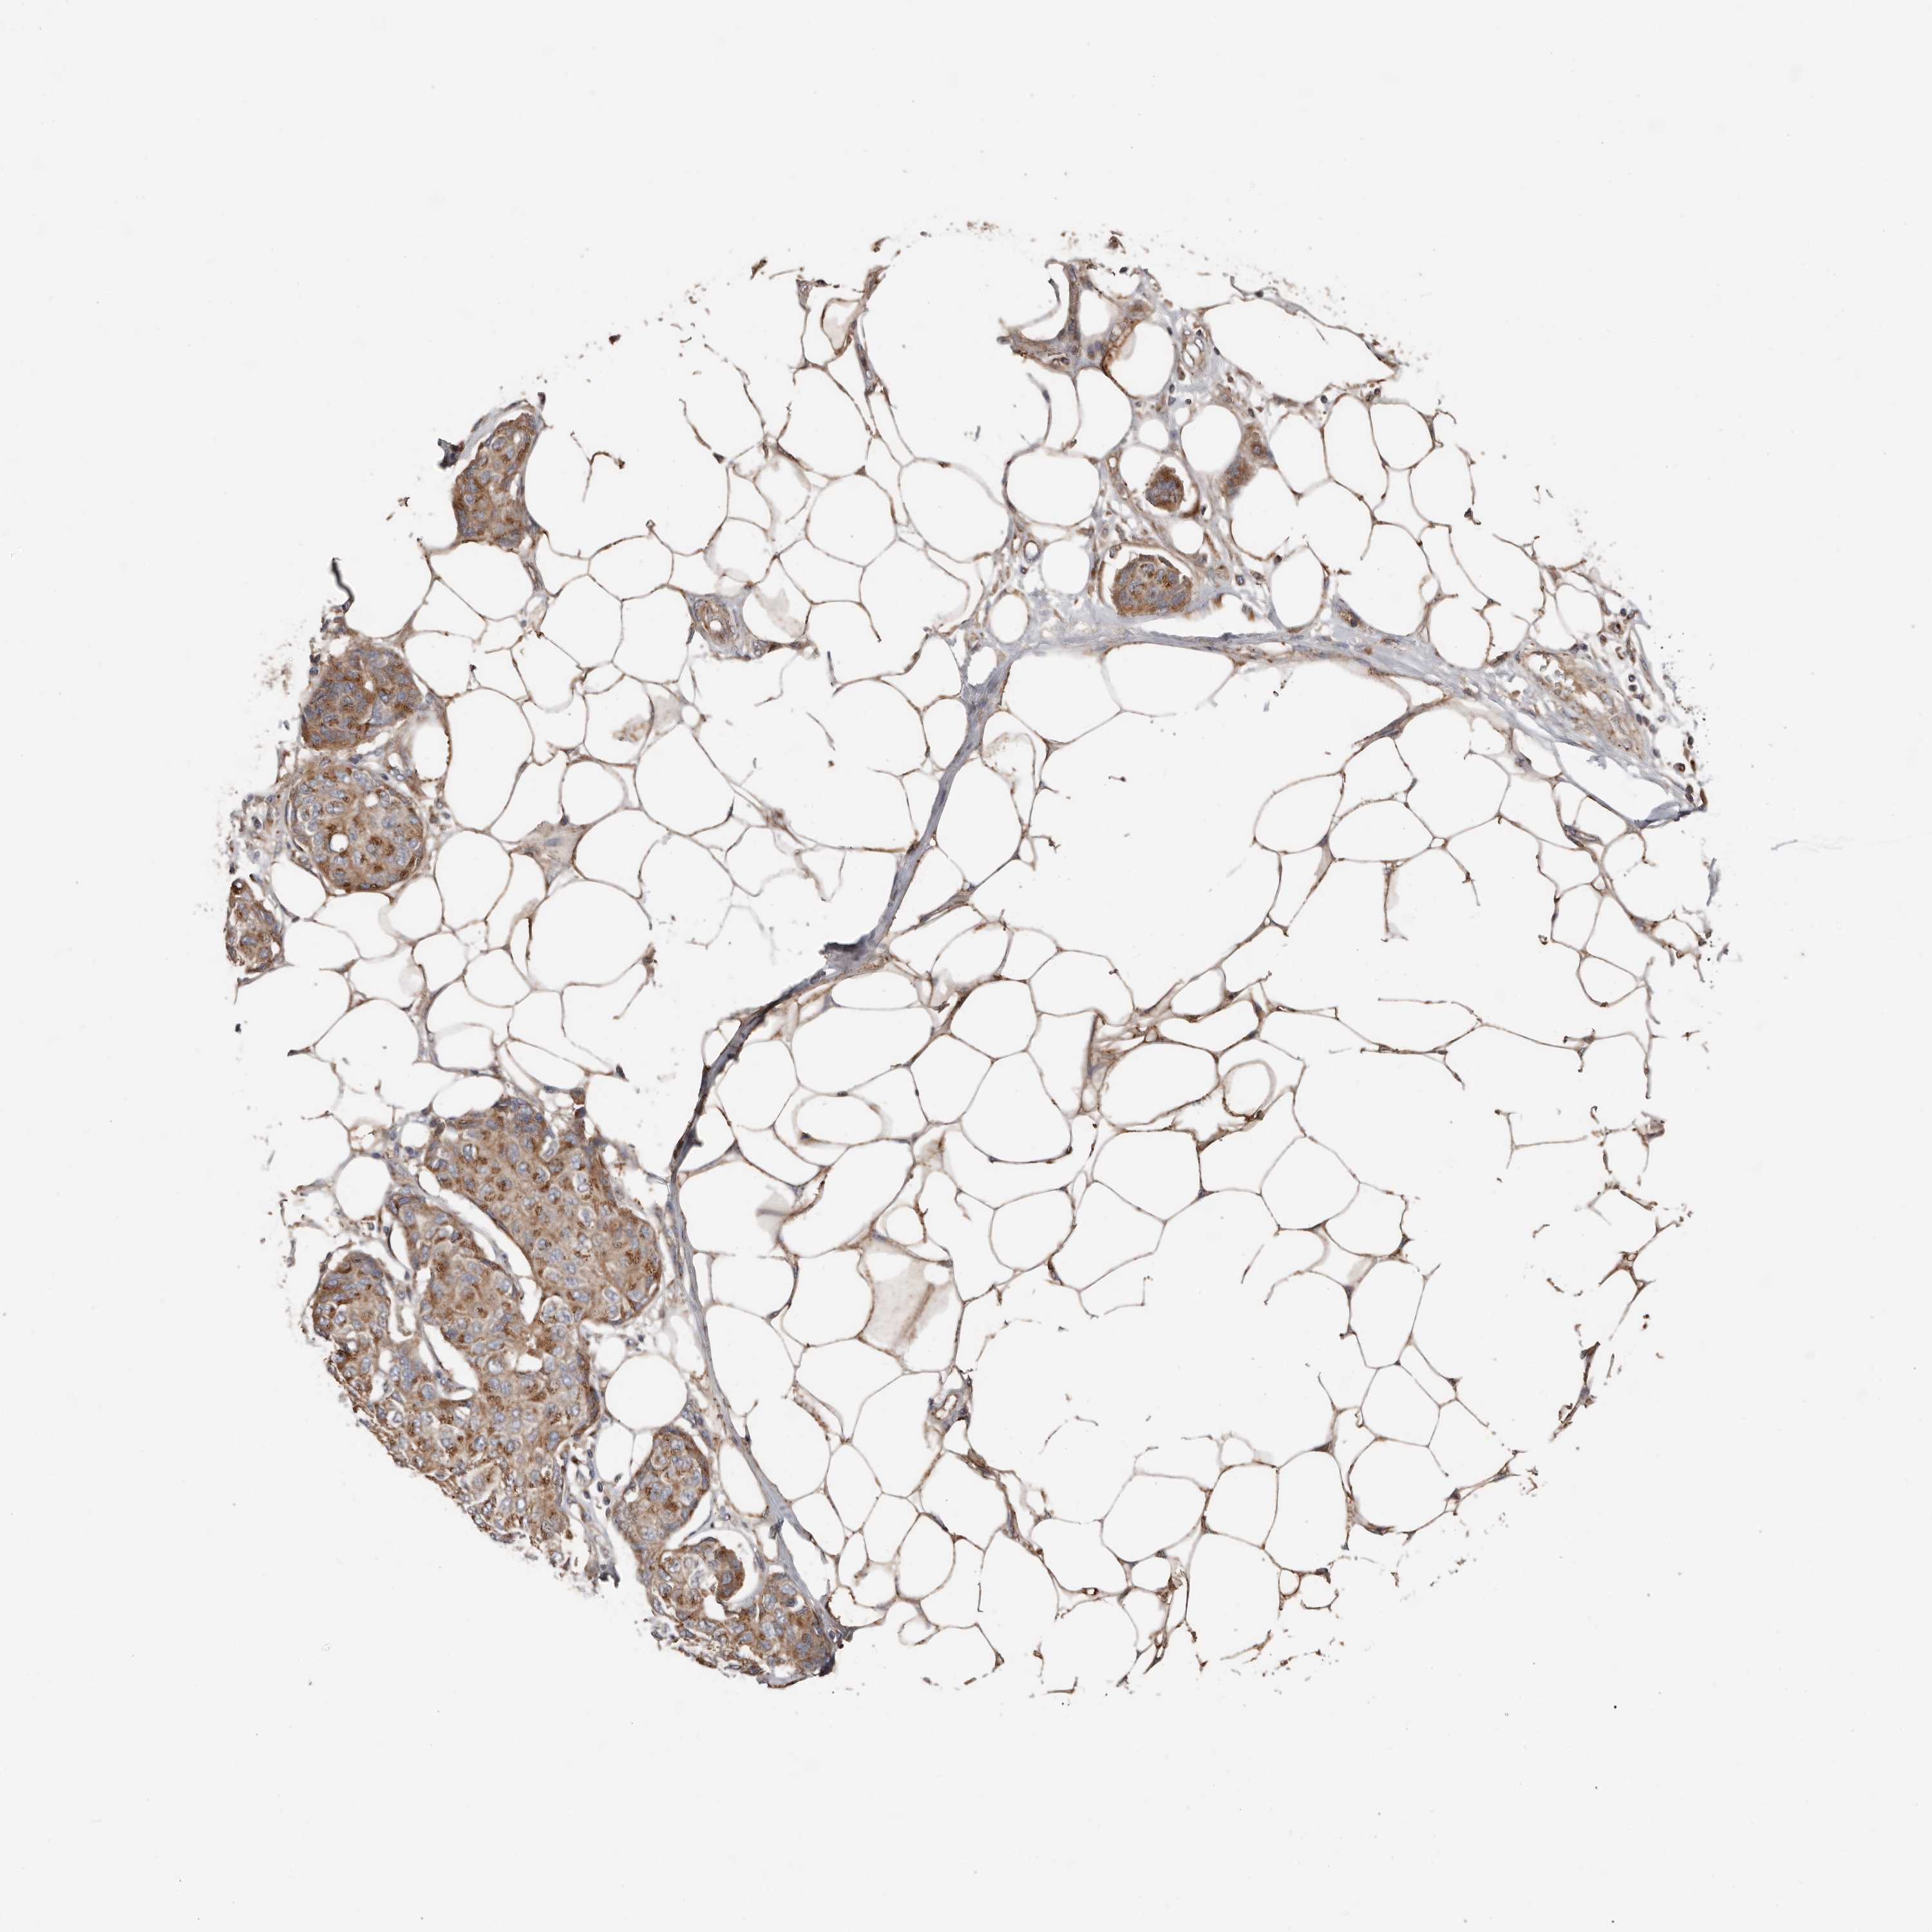

CANCER BREAST CANCER Show tissue menu

BRCA TCGA BRCA VALIDATION PROTEIN EXPRESSION